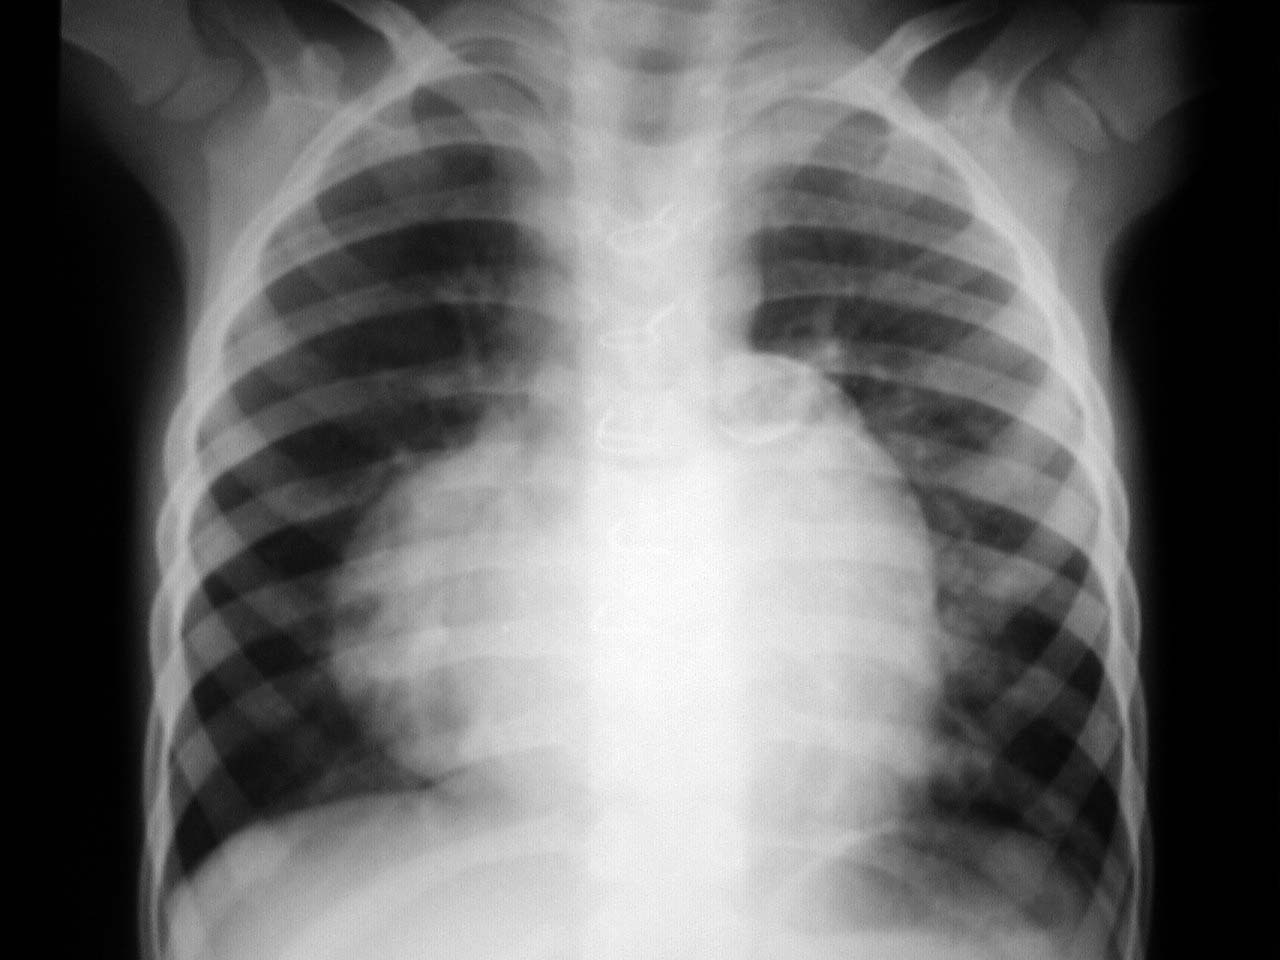

Signo de tetralogía de Fallot en la radiografía de tórax. La hipertrofia de la pared del ventrículo derecho provoca un desplazamiento lateral del prominente ápex cardíaco, junto con su afilamiento e inclinación hacia arriba, que confiere a la silueta cardíaca la forma de un zueco con punta redondeada.

Recordemos que la tetralogía de Fallot es una malformación cardiaca congénita que provoca cianosis en el recién nacido. Se asocian una estenosis pulmonar infundibular, una comunicación interventricular, la dextroposición de la aorta y la hipertrofia del ventrículo derecho.corazon en bota

Esta imagen corresponde a otro ejemplo de este signo.